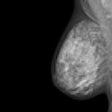

Breast MRI displays viability for new indications